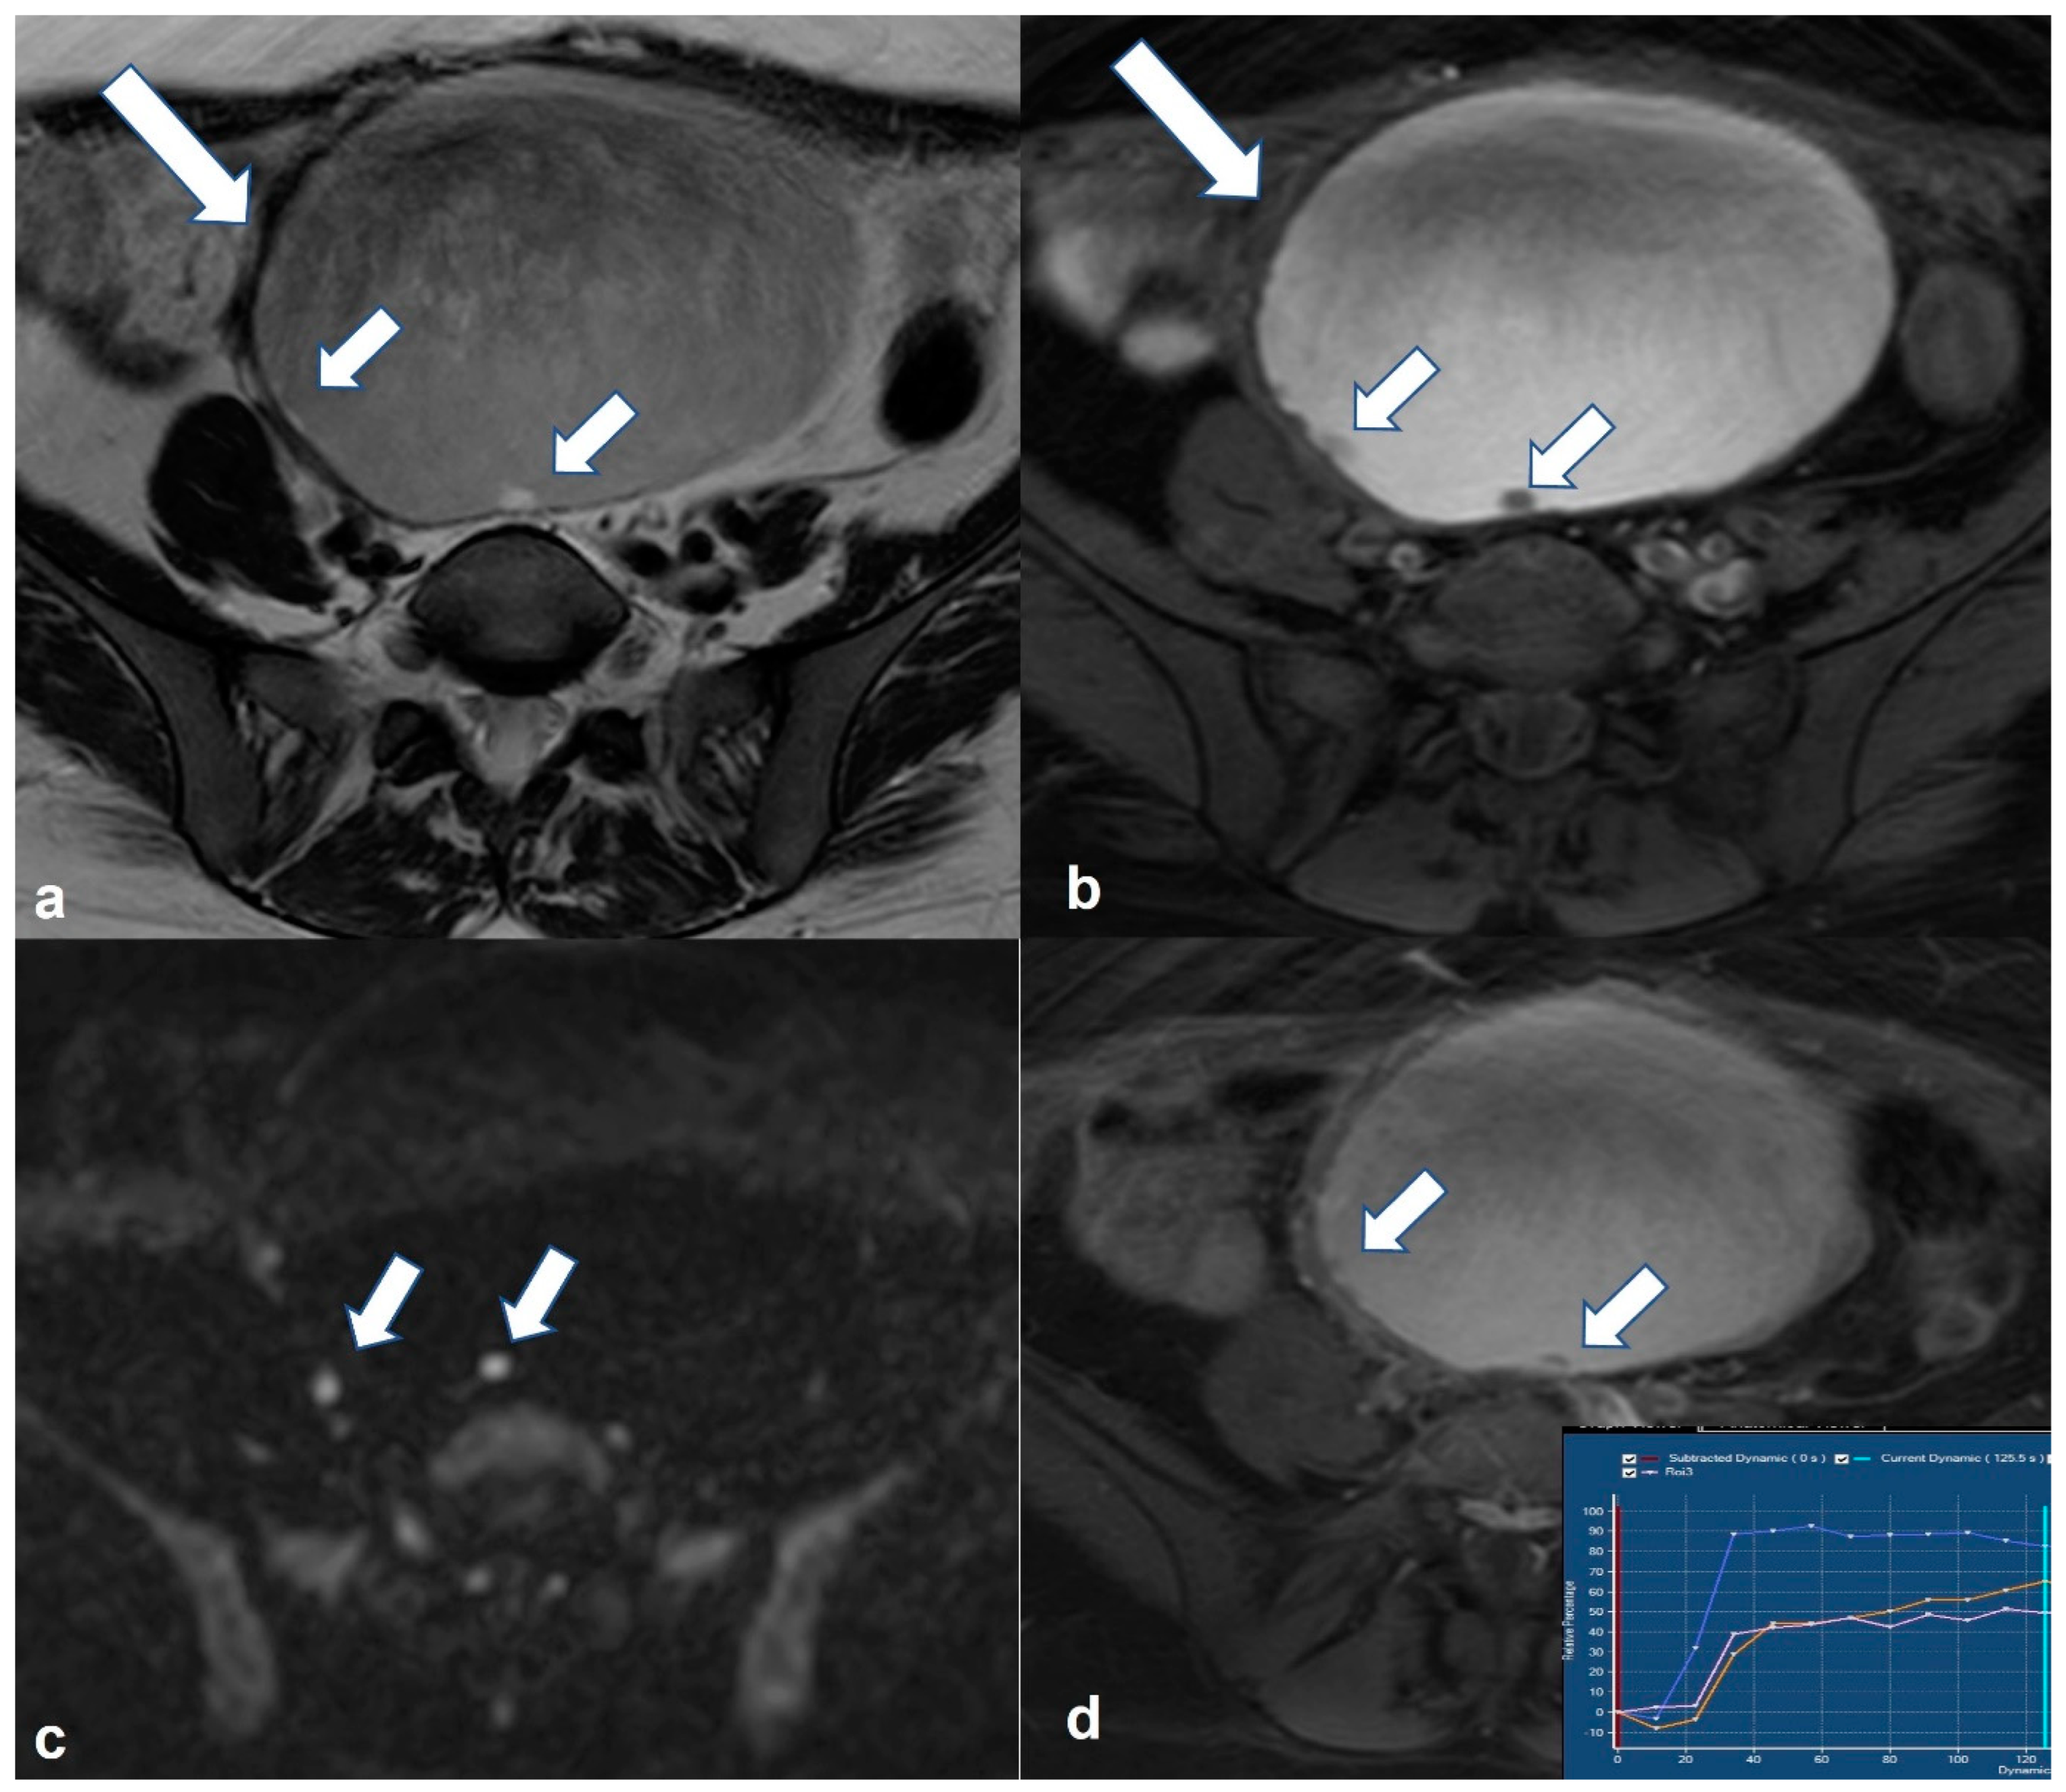

2.5.2. Decidualized Endometrioma

2.5.3. Epithelial Ovarian Cancer